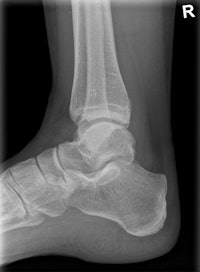

The machine can record static, dynamic, and real-time 3D sequences, and the full range of its potential applications is still to be explored. But there are clinical applications in which it already appears to have advantages over CT, notably in investigations of upper limb fractures in obese patients and weight-bearing lower-limb bone examinations of diabetics, he added.

Shimadzu is promoting the latest version of its digital radiography system, RADspeed Pro. The new EDGE version combines the ease of operation and radiation dose reduction features of the existing platform with a number of new features, according to the manufacturer. It now has a tomosynthesis function, allowing the generation of continuous cross-sectional images based on just one single tomographic scan. There is also dual-energy subtraction software for producing images of soft tissues and bone tissues, as well as an autostitching method for images covering the entire lower extremities or spine.